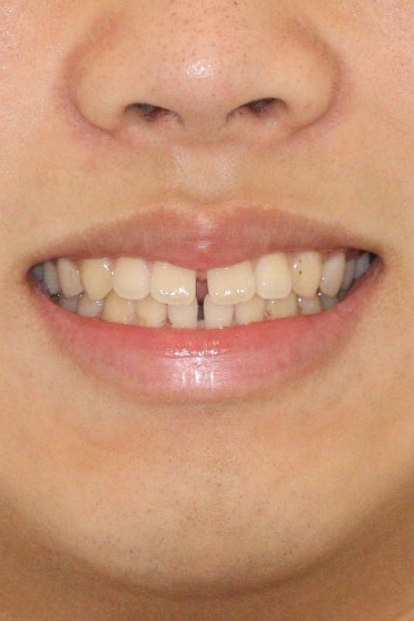

오늘은 아주 간단한 #벌어진앞니 케이스 하나 공유합니다

인비절라인의 가장 기초적인 치료라 치료가 너무 잘되긴 합니다.

치아가 벌어져 오신 분입니다.